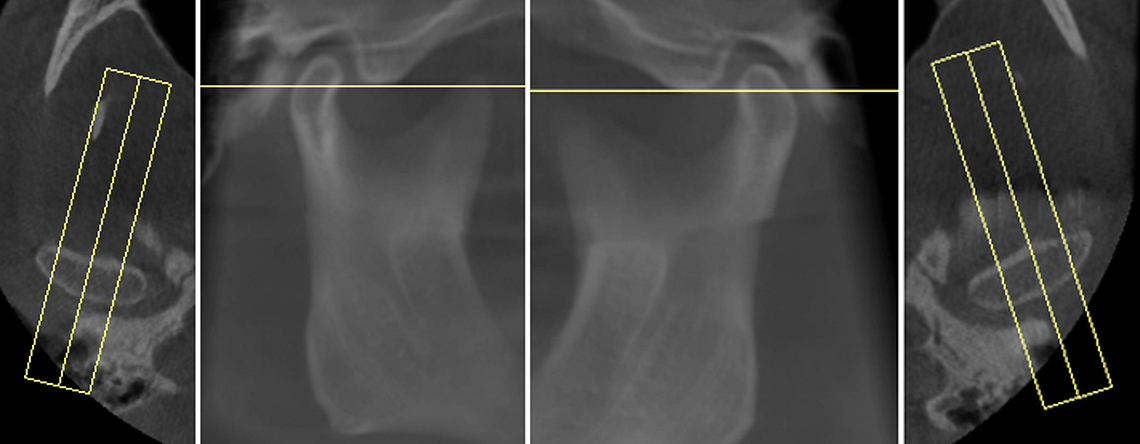

Endodontic Report

Tooth number is selected to analyze the root canal morphology within the CBCT radiograph.

Sagittal and coronal slices and highlighting the angle/curvature/length of the canals.

Measurement of periapical radiolucency volume is a unique advantage with 3D CBCT versus 2D PA. These are endodontic reports for tooth 12 which had a very large periapical radiolucency. The reports were done before and after a long-term calcium hydroxide dressing.